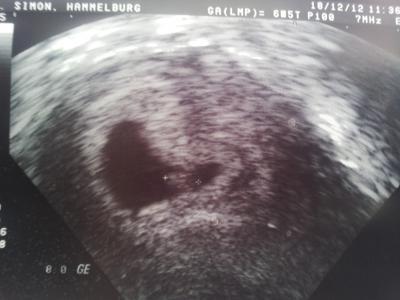

Hallo ihr Lieben!! Ich hatte heute( 6+5)den ersten offiziellen Termin bei meinem Fa. Es wurden alle wichtigen Untersuchungen gemacht, Blut und Pipi abgenommen, und auch Ultraschall. Es ist alles so wie es sein soll, das Würmchen ist jetzt ca 0,8 cm groß. Das Herz schlägt. Die Fruchtblase ist knapp über 2cm groß.Ich freu mich!! Muss am 8.1. wieder hin, bis dahin haben sie auch meinen Mutterpass fertig.

Bild zu ArztBericht mit erstem Bildchen - Forum für August - Mamis